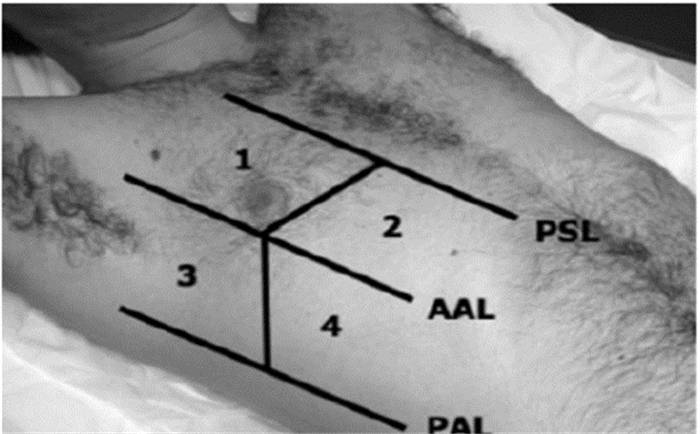

(2)ETUDES方案[22]:2009年又有学者提出了利用肺部超声B线联合脑钠肽(brain natriuretic peptide,BNP)诊断急性心源性肺水肿的ETUDES(emergency thoracic ultrasound in the differentiation of the etiology of shortness of breath)方案,该方案将双侧胸腔分为8个区域,记录各区域B线数目(图 31),双侧胸壁出现3条以上B线的区域越多,心源性肺水肿可能性越大。如每侧胸壁有3个以上区域均有3条以上B线出现则诊断心源性肺水肿可能性超过90%(图 32)。

| 图 31 单侧胸壁分为四区(PSL胸骨旁线;AAL腋前线;PAL腋后线) |

| 图 32 4-B指双侧胸壁(单侧各四个区域)所有区域均出现3条以上B线;3-B指每侧胸壁(单侧各四个区域)至少有3个区域均出现3条以上B线;2-B指每侧胸壁(单侧各四个区域)至少有2个区域均出现3条以上B线;1-B指每侧胸壁(单侧各四个区域)至少有1个区域出现3条以上B线;0-B指所有区域均未出现3条以上B线;1-U指仅有单侧胸壁区域内出现3条以上B线 |